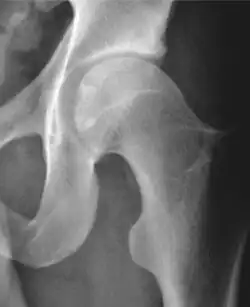

Projectional radiography ("X-ray") is often considered first line for FAI.[10] Anterior-posterior pelvis and a lateral image of the hip in question should be attained.[10] A 45-degree Dunn view is also recommended.[10][19]

| Measurement | Image | Target | Normal value |

|---|---|---|---|

| Center-edge angle of Wiberg | ![]() |

The superior-lateral coverage of the femoral head. | |